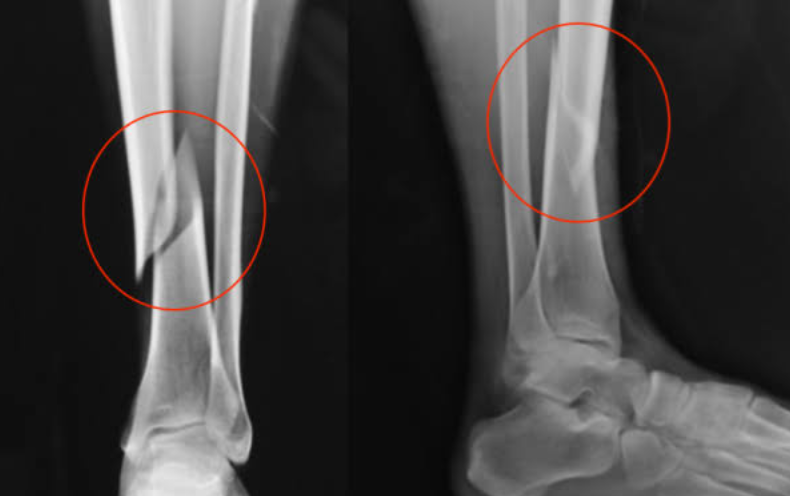

Um raio-X mostra duas fraturas nas pernas da candidata, que segundo informações de outros candidatos estava quase finalizando o teste quando o acidente ocorreu. A cerca de 200 metros a tíbia quebrou e ela foi ao chão.